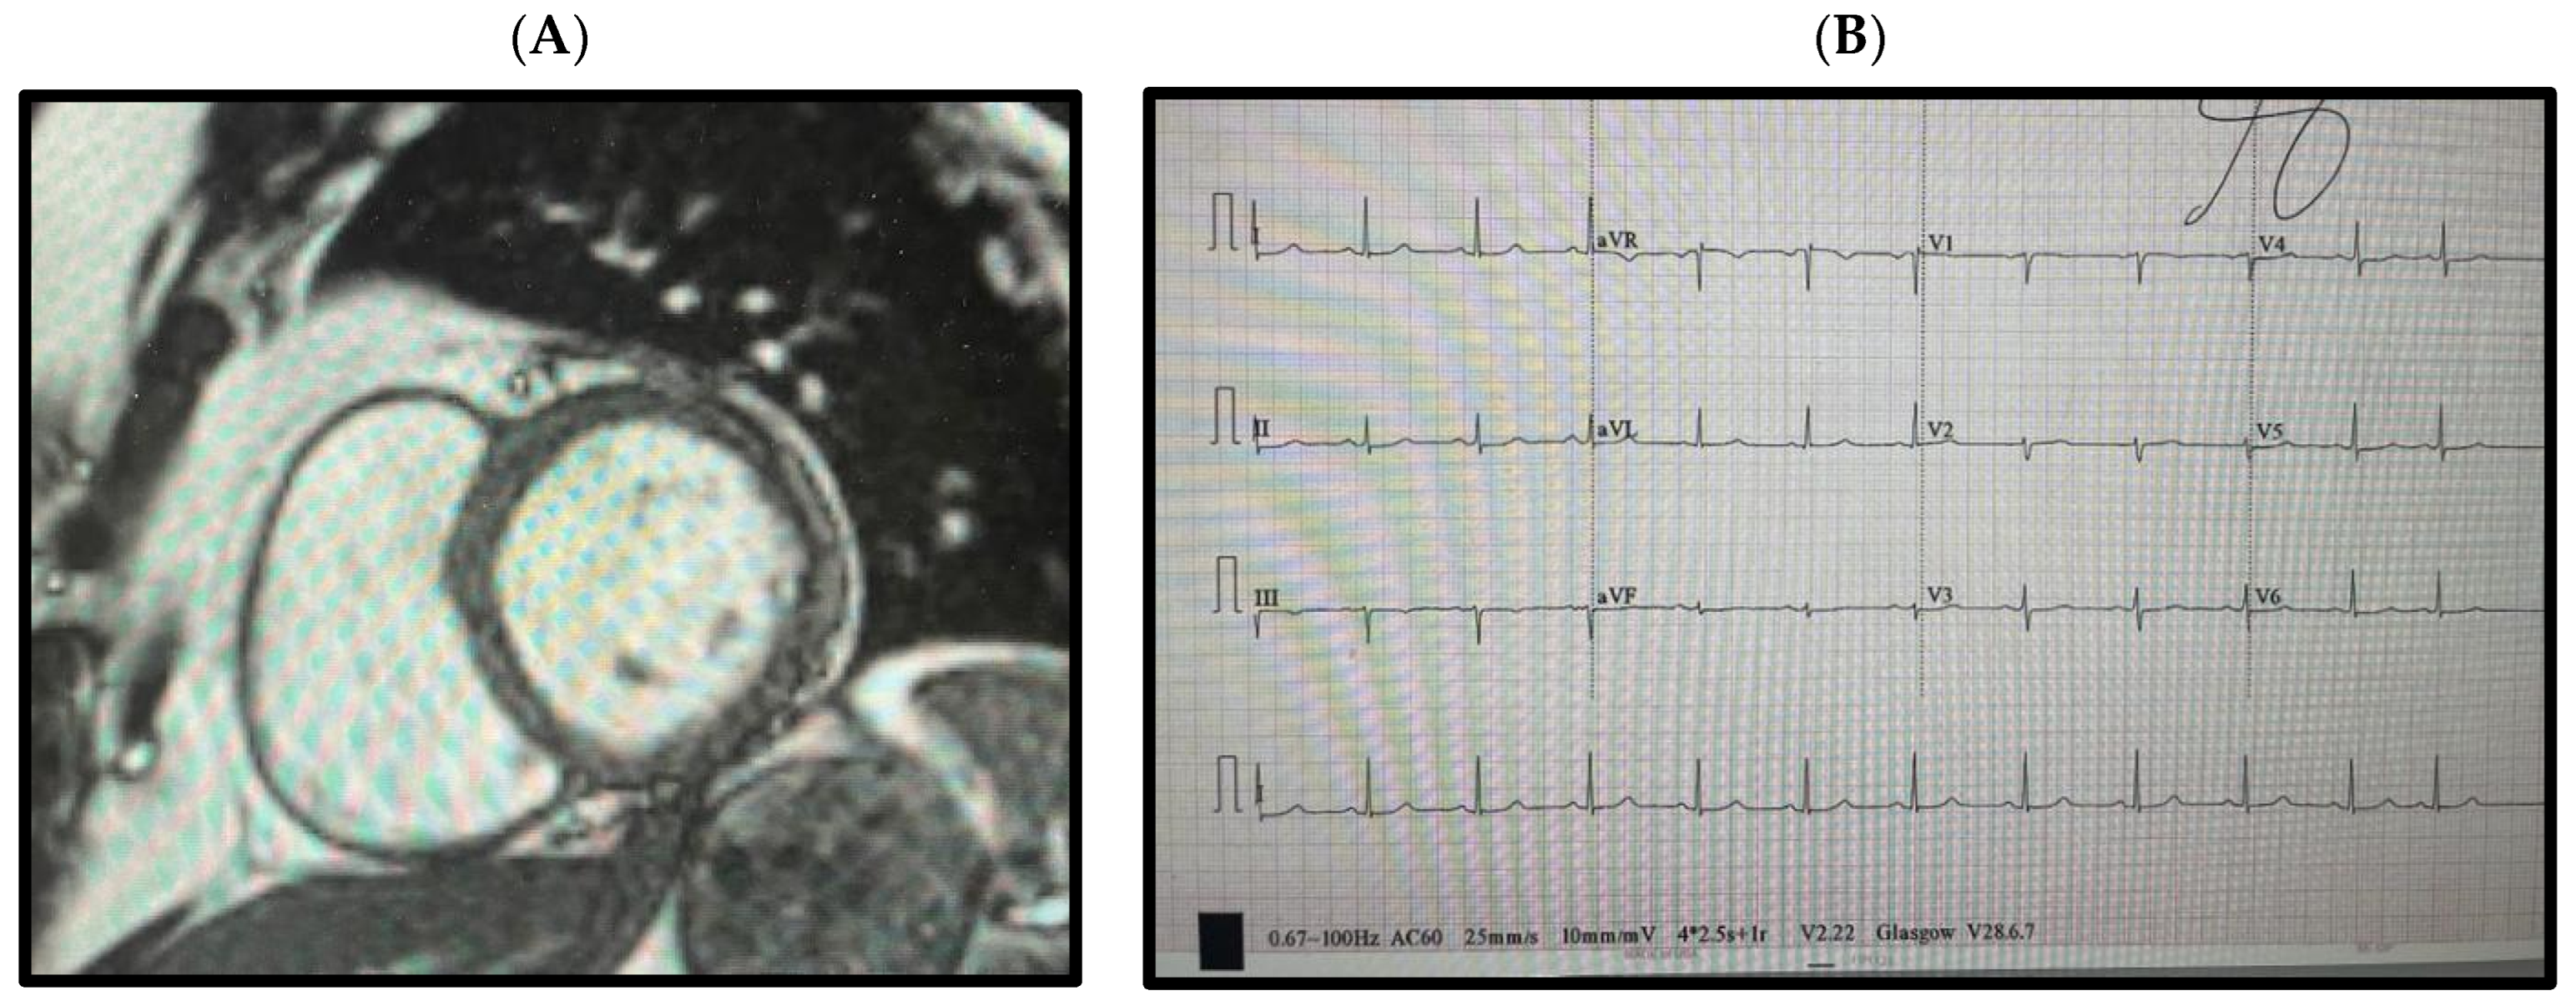

2. Clinical History